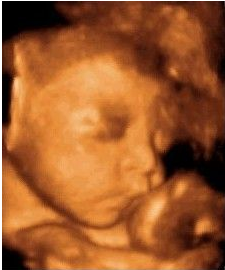

檢查室里面布置的很溫馨,醫(yī)生微笑著接待了我,讓我躺在軟軟的檢查床上,接下來就是期待已久的時(shí)刻了,醫(yī)生先在我肚子上抹了種滑溜溜的東西,然后用掃描儀在肚皮上滾來滾去,奇跡出現(xiàn)啦!屏幕上出現(xiàn)了小寶寶的影像,瞬間覺得奇妙又幸福。出乎我的意料的是畫面十分清晰,不用醫(yī)生解說,我這個門外漢也可以看清楚寶寶的樣子,醫(yī)生說這是從美囯引進(jìn)的ge四維彩超,能夠多角度、全方位的觀察到腹中寶寶的狀態(tài)。

可是寶寶似乎不怎么配合我們,舉著小手擋在臉前,還留給了我們一個美麗的側(cè)臉,這是猶抱琵琶半遮面的節(jié)奏么?看來我家小寶貝兒是個害羞的娃呀。我跟寶寶輕輕說著話,叫它乖寶寶,可是寶寶還是一副我不理你的樣子,這時(shí)醫(yī)生用手輕輕捏了下我的肚子,寶寶這才把臉轉(zhuǎn)了過來,我終于看到寶寶的正面了,簡直是和它媽媽一樣美呆了,嘻嘻。

醫(yī)生一邊給醫(yī)生助理報(bào)數(shù)據(jù),一邊耐心的為我講解,哪里是寶寶的手啊腳啊,之后我們又聽到了臍血流和胎心音,醫(yī)生說寶寶的身體很健康,一切都正常,我這才放心下來。整個四維彩超檢查過程大約持續(xù)1個小時(shí),可我仍覺得意猶未盡,期間還把寶寶的萌照拍了下來,是不是很可愛呢?

做四維彩超所看到的胎兒在宮內(nèi)的情況